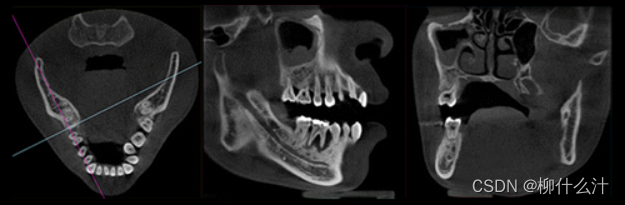

改造可以沿着手动或自动绘制的曲线进行。最常见的是沿牙弓绘制全景曲线,以生成一系列牙齿和骨骼的合成全景图(图00和01)。由于这些合成全景图像的厚度较小,通常不可能在一张图像中看到上下牙弓的情况。因此,通常需要为上、下牙弓分别绘制曲线(图02)。另外,可以计算出这些合成全景图的射线和,类似于从全景X光片上获得的图像。图23显示了不同厚度的合成全景堆叠的射线和全景图像。

沿着用户在轴向平面(左)绘制的曲线合成的全景图像(右)。

沿着与图20所示的曲线略微靠前或靠后的地方,额外的合成全景图像。